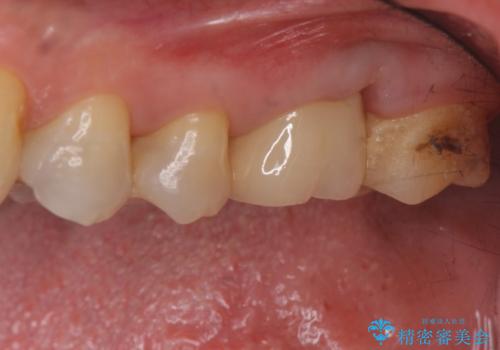

検査で見つかった虫歯 セラミッククラウンでの治療

- 検査の結果被せ物の下に虫歯が確認された患者様です。

虫歯を取りきった後セラミッククラウンでの修復処置を行います。

被せ物の裏側の虫歯は被せ物を取らないと除去できません。

今回は過去に治療された部分をすべてやり直しました。